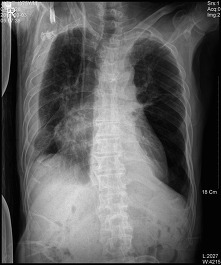

* CHEST PA (흉부 촬영)

♣검사목적

폐렴을 구분하거나 폐병소의 위치를 결정할 수 있다.

Central Ray

T-6 높이의 정중면에 수직으로 입사

Check Point

양측 쇄골의 휴골단은(sternal end)은 척추로부터 같은 거리에 놓여야 한다.

3~5cm의 폐첨부(apex)가 쇄골위에 보여야 한다.

posterior rib이 diaphram위에 보여야 한다.

척추로 부터 늑골의 외측연까지 거리는 양측 모두 같아야 한다.

심장 음영의 일부가 척추의 오른쪽에 나타나야 한다

심장과 diaphram의 윤곽은 뚜렷해야 한다

흉추와 양측 rib의 희미한 음영(faint shadow)이 심장 음영을 통해 보여야   한다.